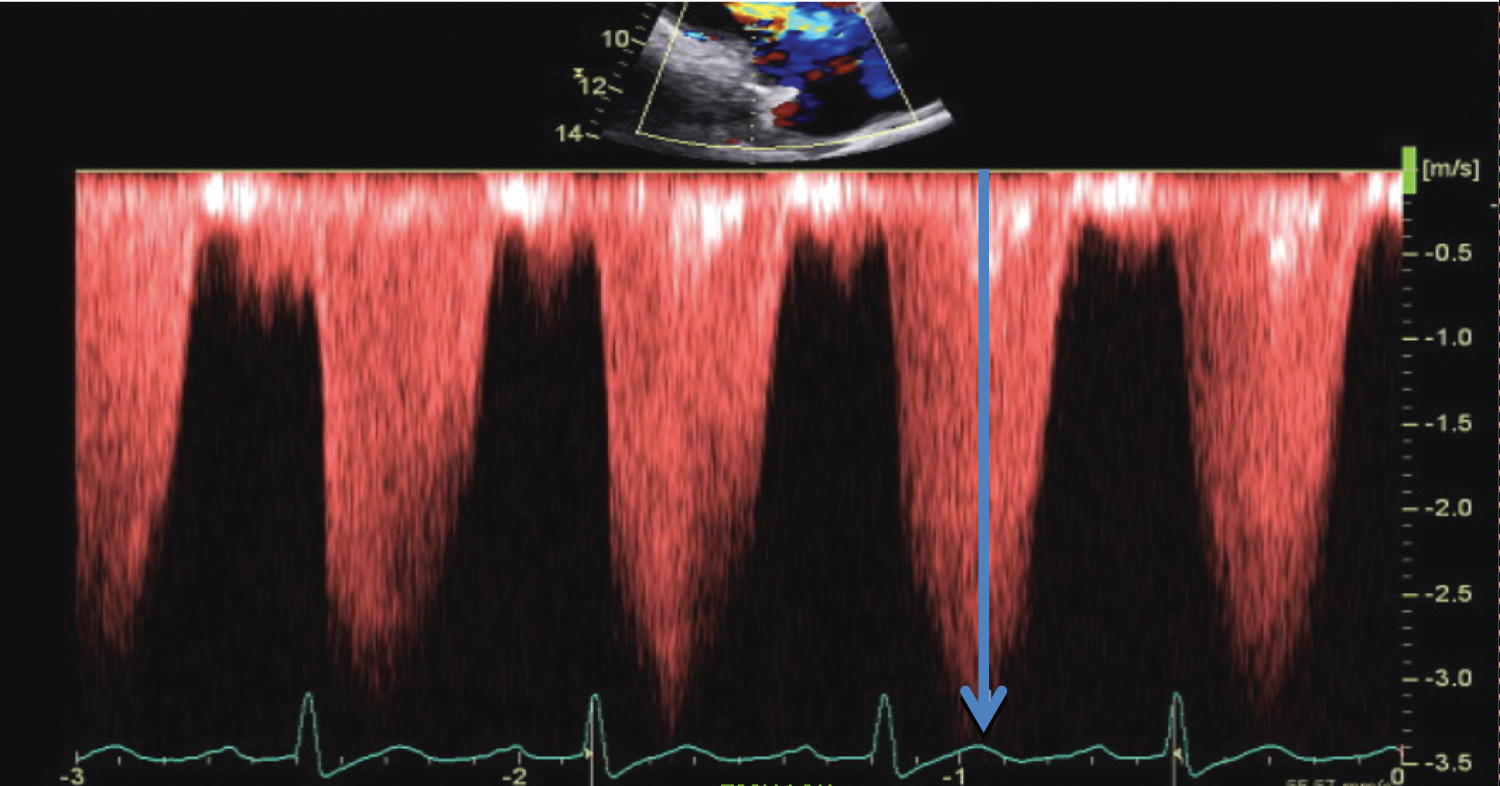

Treatment with a diuretic, beta-blocker, and intravenous nitroprusside resulted in a BP = 150/90 and HR = 95 bpm. Oxygenation was adequate with assisted ventilation. Urgent echocardiography revealed left ventricular (LV) systolic function was depressed with an ejection fraction of 20%, dilated right ventricle (RV) with severe reduction of RV systolic function, severe tricuspid regurgitation (TR) and elevated right heart pressure (Figure 2). Incidentally, an atrial septal defect (ASD) was identified.

Figure 2: TR envelope: Blue arrow to 3.5 m/sec. The RV-RA gradient is approximately 50 mmHg. View Figure 2